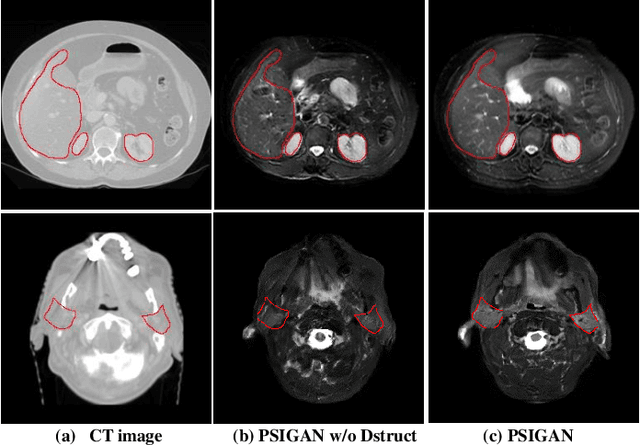

Abstract:We developed a new joint probabilistic segmentation and image distribution matching generative adversarial network (PSIGAN) for unsupervised domain adaptation (UDA) and multi-organ segmentation from magnetic resonance (MRI) images. Our UDA approach models the co-dependency between images and their segmentation as a joint probability distribution using a new structure discriminator. The structure discriminator computes structure of interest focused adversarial loss by combining the generated pseudo MRI with probabilistic segmentations produced by a simultaneously trained segmentation sub-network. The segmentation sub-network is trained using the pseudo MRI produced by the generator sub-network. This leads to a cyclical optimization of both the generator and segmentation sub-networks that are jointly trained as part of an end-to-end network. Extensive experiments and comparisons against multiple state-of-the-art methods were done on four different MRI sequences totalling 257 scans for generating multi-organ and tumor segmentation. The experiments included, (a) 20 T1-weighted (T1w) in-phase mdixon and (b) 20 T2-weighted (T2w) abdominal MRI for segmenting liver, spleen, left and right kidneys, (c) 162 T2-weighted fat suppressed head and neck MRI (T2wFS) for parotid gland segmentation, and (d) 75 T2w MRI for lung tumor segmentation. Our method achieved an overall average DSC of 0.87 on T1w and 0.90 on T2w for the abdominal organs, 0.82 on T2wFS for the parotid glands, and 0.77 on T2w MRI for lung tumors.